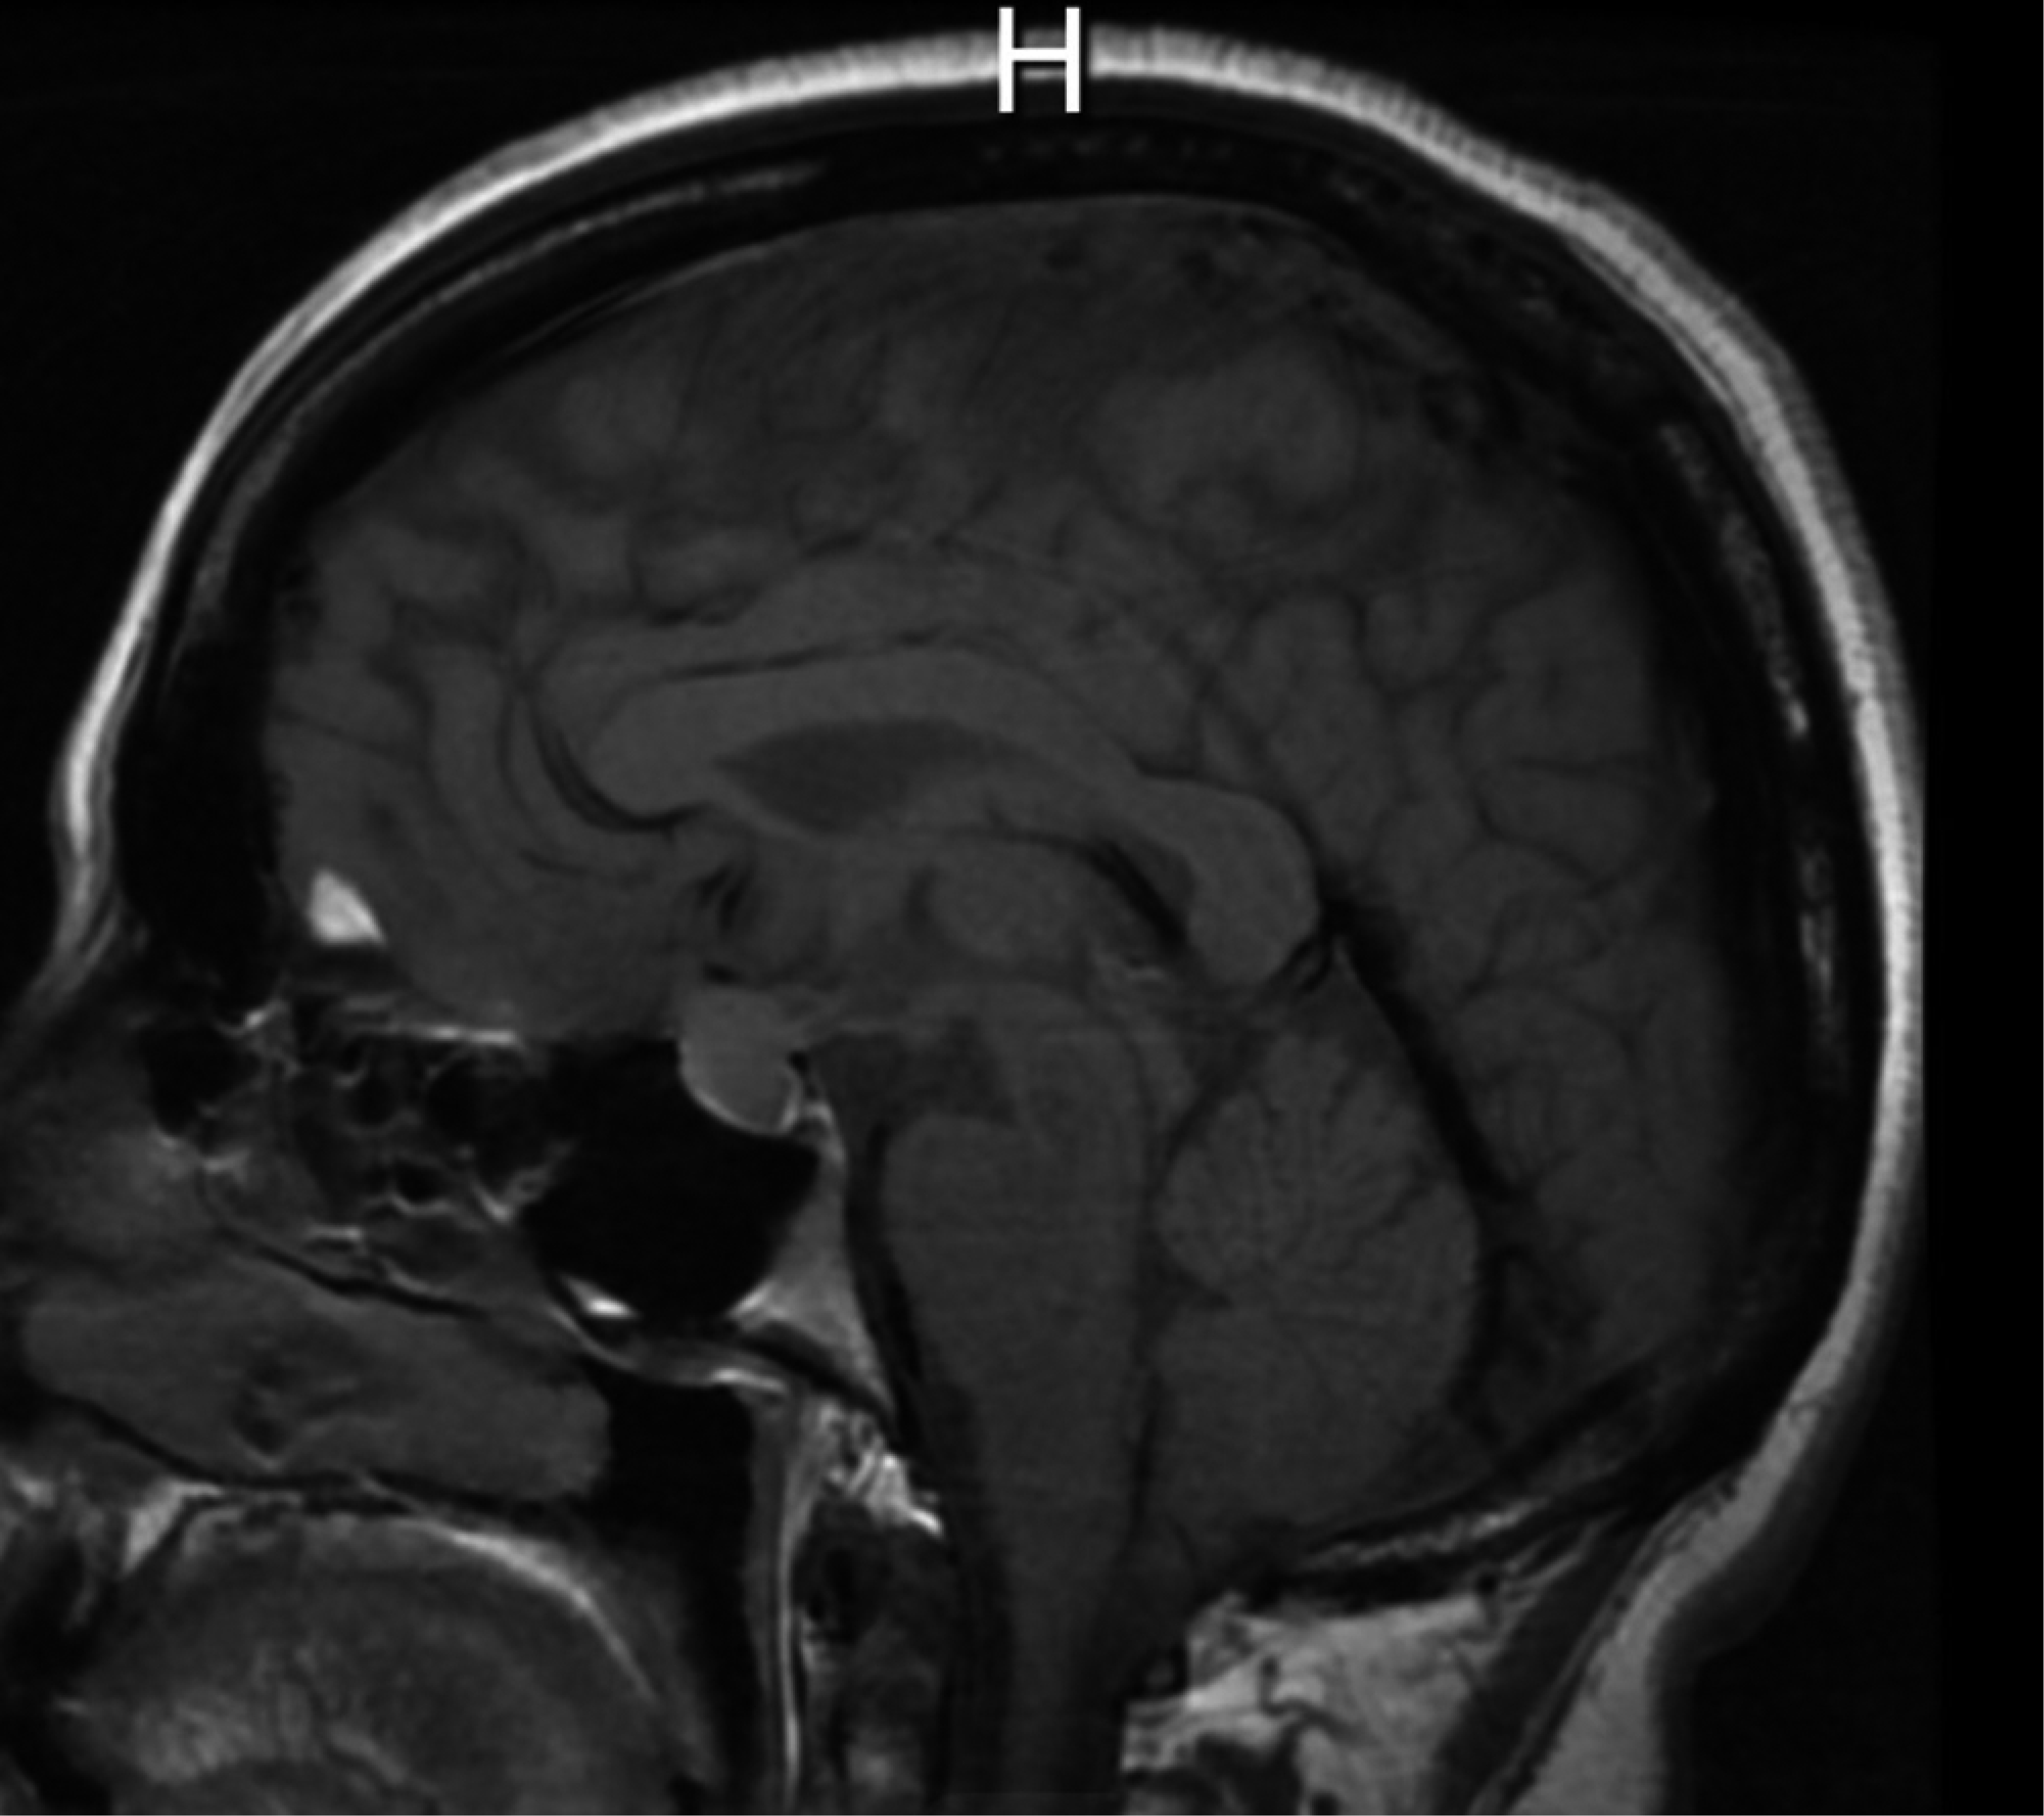

Se trata de mujer de 45 años que inició padecimiento en el 2018 con presencia de cefalea, fue tratada con analgésicos y hemianopsia bitemporal de predominio izquierdo, por lo que acudió a realizarse tomografía axial computarizada (TAC) simple y contrastada de cráneo, en donde se identificó lesión selar. Continuó con protocolo diagnóstico con imagen por resonancia magnética (IRM) de cráneo y se encontró lesión selar (Figura 5). Se inició protocolo preoperatorio solicitando los siguientes estudios: campimetría visual computarizada con hemianopsia bitemporal, perfil hormonal sin alteraciones, laboratorio paraclínico normal, radiografía de tórax, electrocardiograma normal y valoración preoperatoria por parte de los servicios de medicina interna y endocrinología para recibir recomendaciones sin contraindicación.

Diagnóstico por imágenes. La placa simple de cráneo en perfil estricto muestra en 80% de las lesiones sintomáticas abombamiento y erosión de la silla turca.6 En la TAC de cráneo estos quistes son en general hipodensos. En algunas ocasiones con realce al contraste en forma de anillo, en especial cuando presentan focos de epitelio escamoso.1-4,9 La IRM de cráneo muestra la extensión supraselar de estas lesiones, la relación con los nervios ópticos, quiasma e hipotálamo.1,9,10

Figura 5